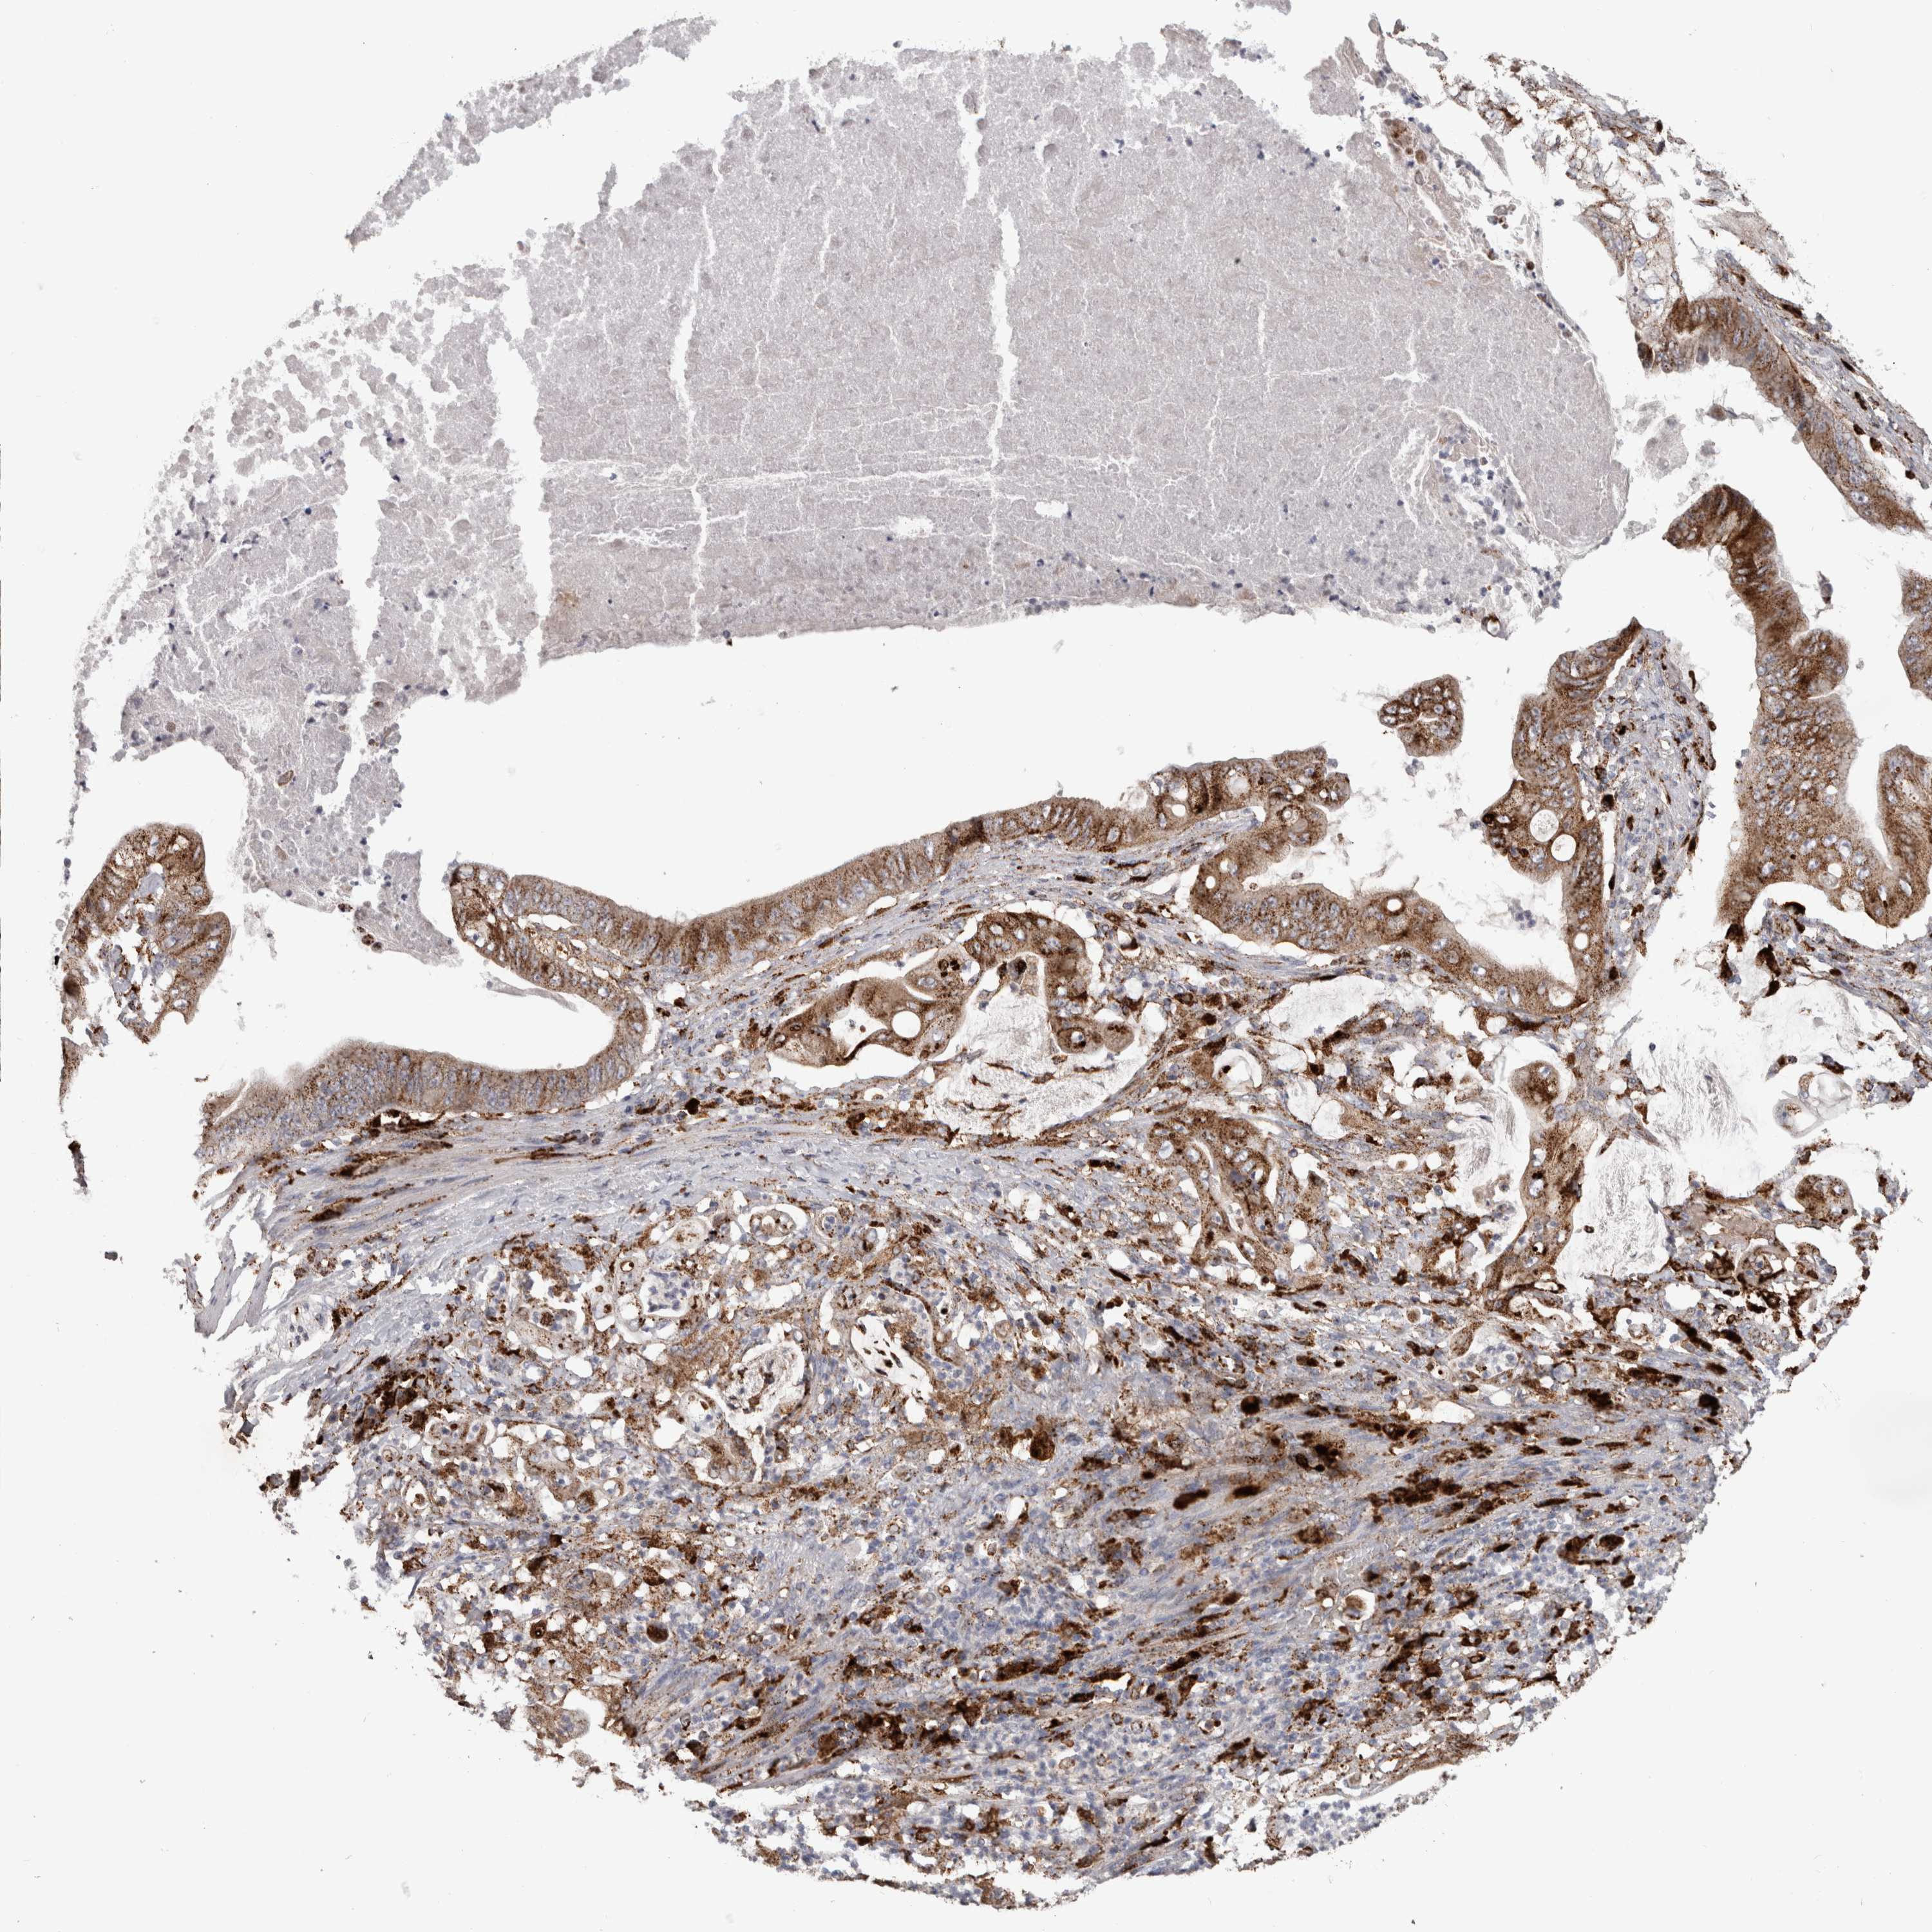

STOMACH CANCER - Protein expressioni

A mouse-over function shows sample information and annotation data. Click on an image to view it in a full screen mode. Samples can be filtered based on level of antibody staining by selecting one or several of the following categories: high, medium, low and not detected. The assay and annotation is described here.

Note that samples used for immunohistochemistry by the Human Protein Atlas do not correspond to samples in the TCGA dataset.

Antibody stainingi

Antibody staining in the annotated cell types in the current human tissue is reported as not detected, low, medium, or high, based on conventional immunohistochemistry profiling in selected tissues. This score is based on the combination of the staining intensity and fraction of stained cells.

Each image is clickable and will lead to virtual microscopy that enables deeper exploration of all samples and also displays staining intensity scores, fraction scores and subcellular localization as well as patient and tissue information for each sample.

Antibody HPA049876

Antibody HPA053504

Antibody CAB025114

Staining

High

Medium

Low

Not detected

Intensity

Strong

Moderate

Weak

Negative

Quantity

>75%

75%-25%

<25%

None

Location

Nuclear

Cytoplasmic/membranous

Cytoplasmic/membranous,nuclear

Adenocarcinoma, NOS